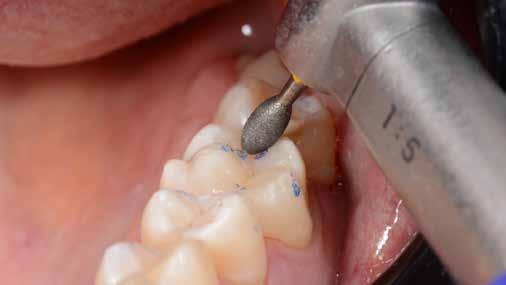

Az 53 éves hölgy páciens jobb felső 6-os fogában látható amalgámtömés cseréje volt a cél. A tömés mellett secunder caries és az amalgám következtében létrejött mesialis zárólécen áthaladó repedés, továbbá mesialis caries figyelhető meg (1. ábra). El kellett kerülni, hogy a tömés kifúrásakor az amalgámtörmelék a páciens szájába kerüljön, esetleg ebből valamennyit lenyeljen, a kezelés első lépésként kofferdám izoláció került fel a jobb felső kvadránsba (2. ábra). A kapocs a 1.7 fogra került, ezzel kényelmesen helyet teremtett a későbbiekben felkerülő matricarendszernek. Az egyszerre több fog izolálása lehetővé teszi, hogy a szomszédos fogak referenciául szolgáljanak a restauráció felépítése közben.

A régi amalgámtömés eltávolítását követően caries indikátor segítette a carieses laesio megfelelő kitisztítását a pulpa expozíciója nélkül. Ezután kerülhetett sor az ideális üregdesign kialakítására, továbbá a zománcszélek finírozására (3. ábra) Az approximális box megnyitása során az alátámasztatlan zománcprizmák eltávolításra kerültek, ezzel is csökkentve a secunder caries képződés veszélyét. Az így kialakuló forma elősegíti a matrica megfelelő adaptációját, végül pedig az approximális box határainak a hozzáférhetőségét, így finírozás során ez jobban kontrollálható és polírozható.

A Palodent V3 matricarendszer felhelyezését követően a zománc 10 másodperces szelektív savazása, majd lemosása és leszárítása után történt a kavítás bondozása Prime & Bond Universallal.